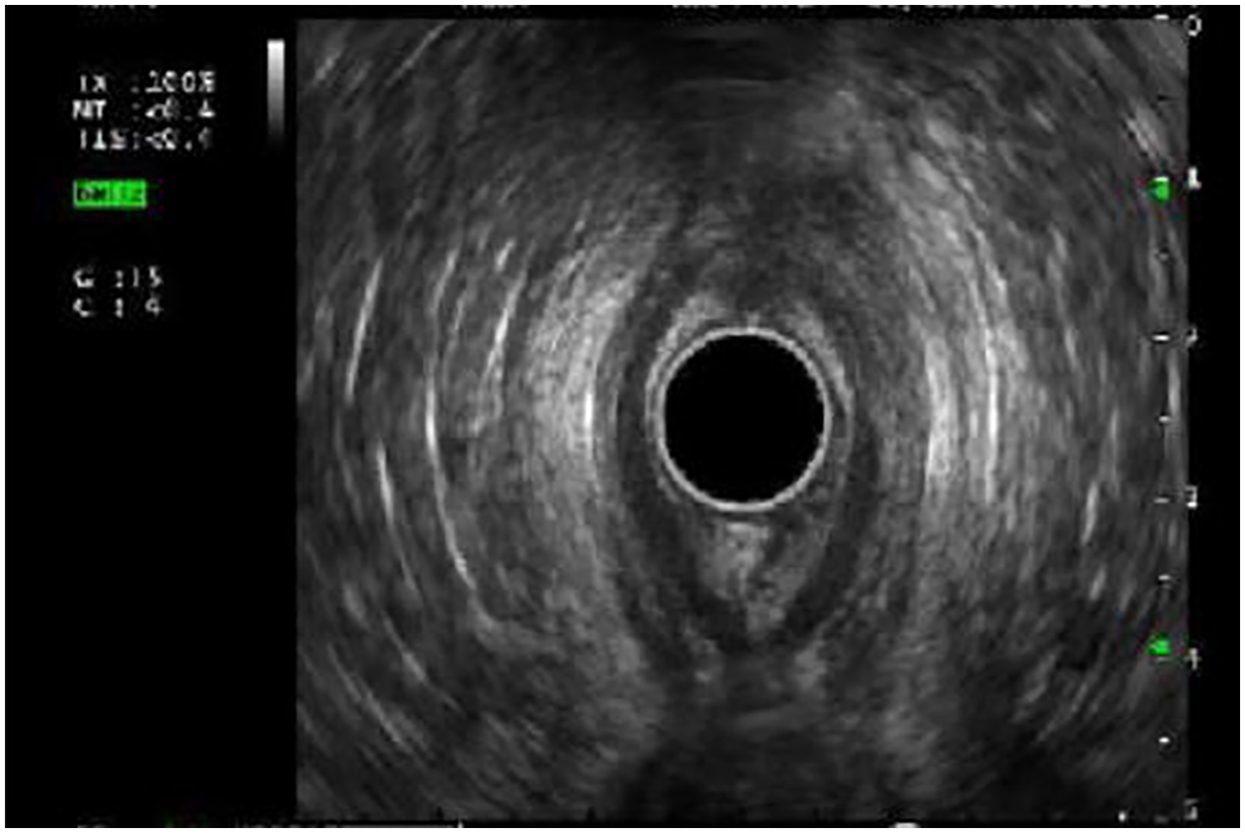

EUS was used to evaluate the esophageal wall for long-term complications associated with eosinophilic esophagitis (15 EUS), esophageal strictures (19 EUS) and subepithelial lesions (6 EUS). Esophageal wall compliance was assessed with tissue elastography in eosinophilic esophagitis with suspected fibrosis. Stiffness (by elastography) and fibrosis (histologically) (Figures 2A,B) reverted after 6-month treatment of monoclonal antibody therapy, antibody against IL-4 receptor α chain (IL4Rα) in three patients who had EUS pre and post treatment (Table 3).

Figure 2. (A) Esophageal wall thickness prior to IL-4Rα antibody treatment. (B) Elastography demonstrating concerns for esophageal wall stiffness.